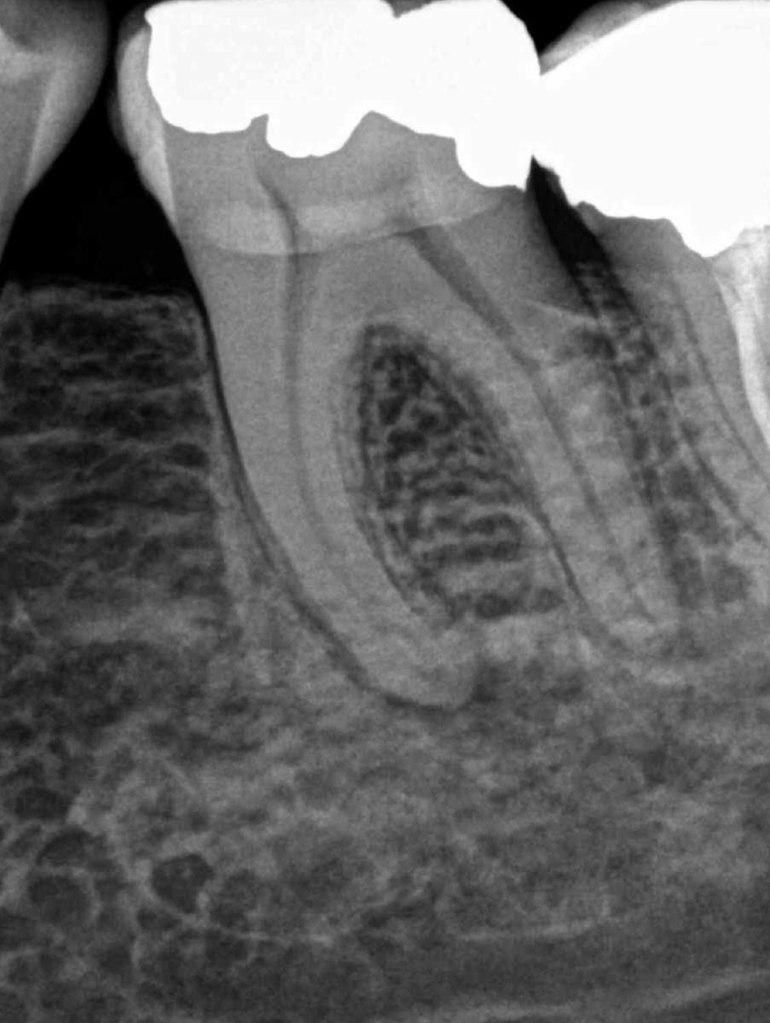

Reco pared vesticular